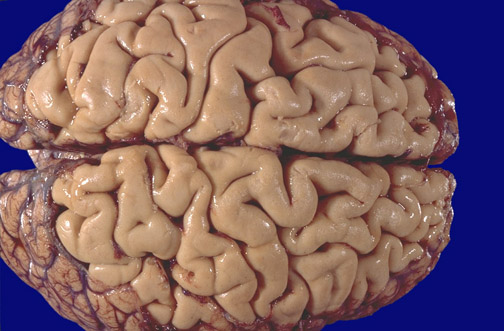

The meninges have been removed at the vertex of a normal brain to reveal the Rolandic fissure with the precentral gyrus (motor cortex) and the postcentral gyrus (somesthetic cortex).